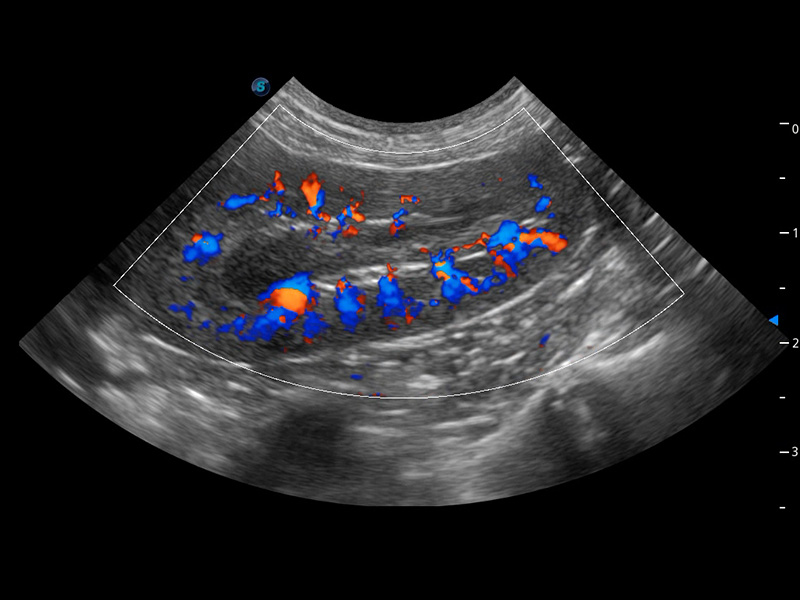

ProPet 60 作為一款高端臺式動物超聲設(shè)備,為動物醫(yī)生的日常診斷提供了一系列貼合動物臨床需求、解決臨床實際問題的高級成像功能。憑借全系列高清探頭,滿足醫(yī)生對腹部、心臟、生殖、淺表、肌骨等成像的所有需求,切實幫助您提升檢查效率,提高診斷信心。

獸用彩色多普勒超聲診斷系統(tǒng)